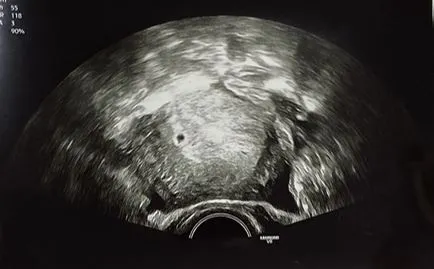

의사 선생님께서 초음파를 보시더니 하시는 말씀,

"축하드립니다. 임신 4-5주차 정도 된 것 같아요. 다음 주에 다시 한 번 오셔서 확인해봐야 정확한 주수를 알 수 있을 것 같아요."

erer.JPG?type=w1 임신 4주차 초음파